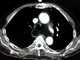

Mediastinal lipomatosis